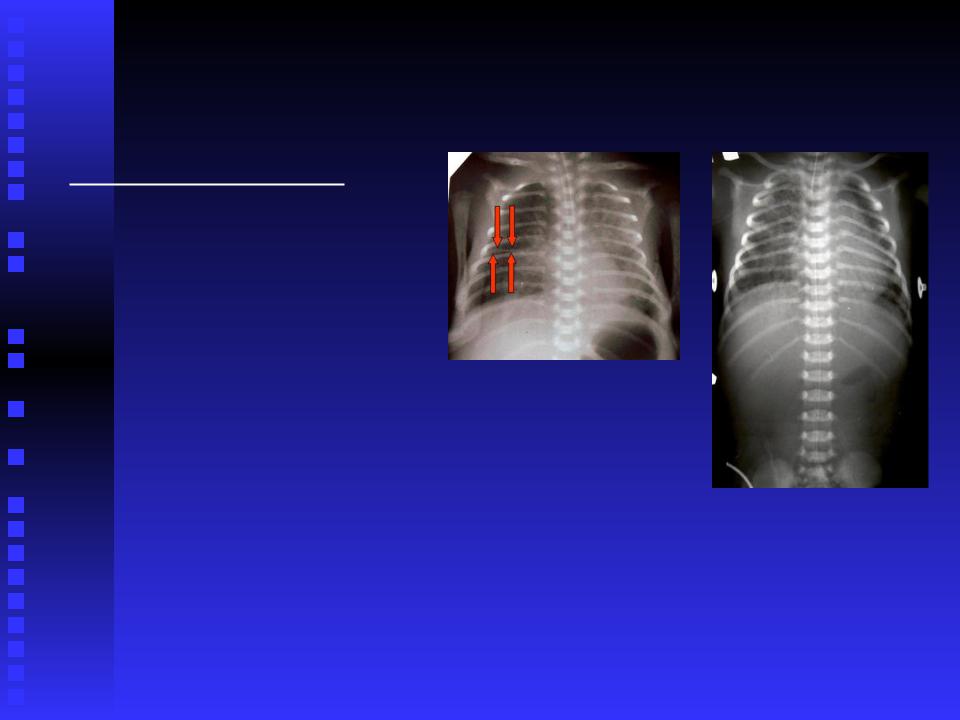

Дифузні зміни на

рентгенограмі.